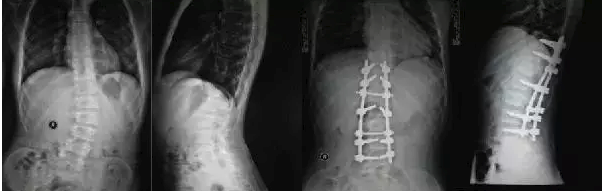

但是有一些孩子在五六岁,或者七八岁就出现了严重的脊柱侧弯,需要手术治疗。那这个时候呢就需要做叫生长棒的手术,那这个生长棒手术的最佳治疗年龄,一般是在五岁以后、七八岁是最合适的。

但是对于有一些脊柱侧弯,他是单纯由于半椎体畸形引起的。那么我们做半椎体的切除,上下的融合阶段呢只有那么两到三个阶段。这个时候呢对孩子的脊柱生长发育的影响不大,那就可以早一些治疗甚至一到两岁就可以做这个手术了。